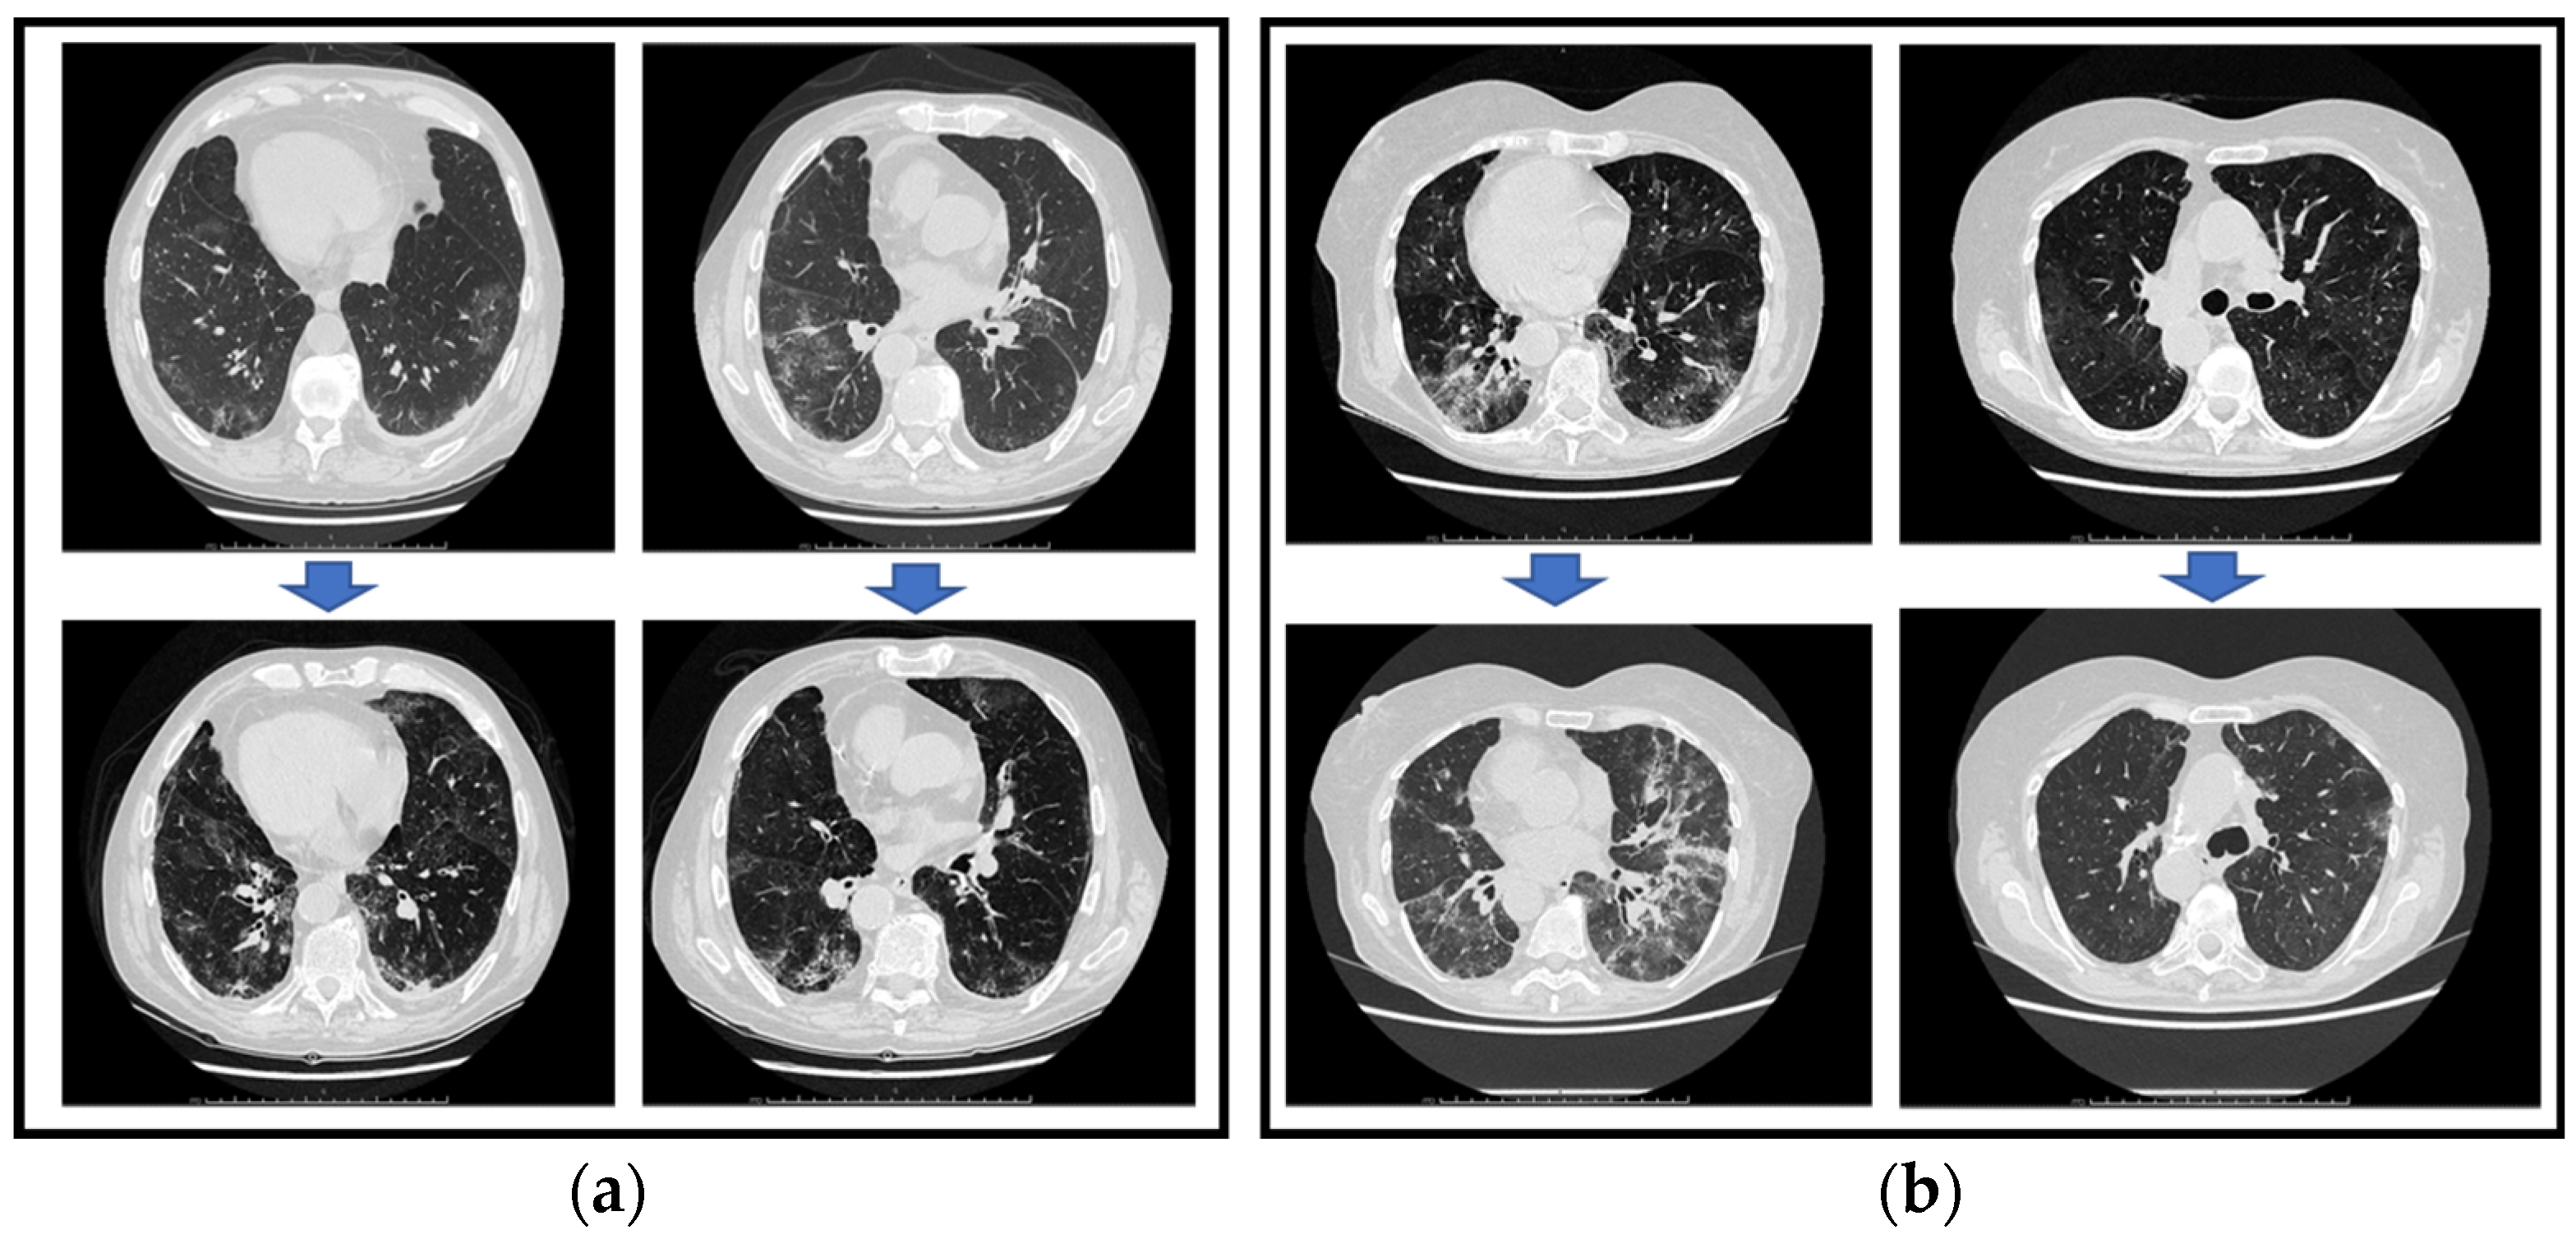

2. Detailed Case Descriptions